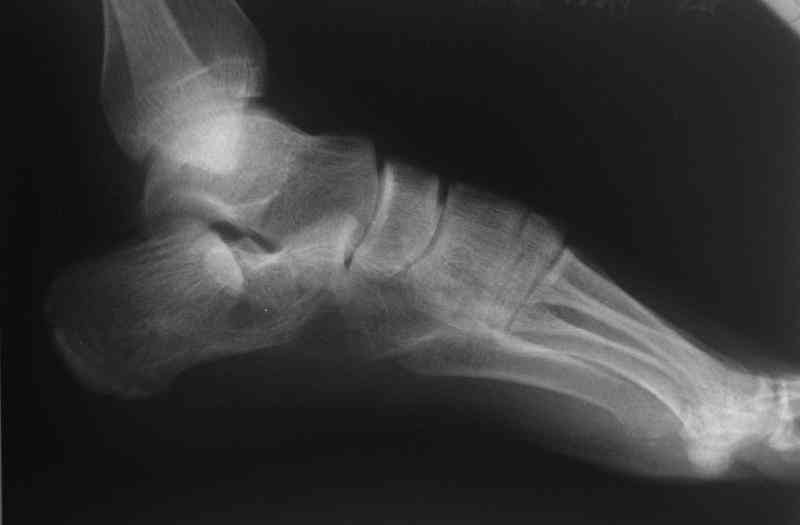

Если я правильно понял, вы хотели спросить: "Что делать с кистой, и как на этом фоне выполнять репозицию и фиксацию перелома?"

Я думаю, что для начала нужно выполнить КТ пяточной кости и определиться с границами полости. Не исключено, что отрывной перелом верхнего полюса бугра носит патологический характер (верхняя стенка кисты).

Its a comminuted one.

I would have a CT prior 2 surgery(If u have to postpone a surgery for it - I would operate without one)

Если нет опыта в остеосинтезе пяточной пластиной то лучше начать с экскохлеации полости кистозного образования и заполнения его остеоиндукторами Коллапан, Тутопласт, etc.Закрытая репозиция с рентгенконтролем на столе и перкутанная фиксация спицами пяточного бугра с фиксацией в эквинусе могут дать вполне приемлемый результат.

Сустав похоже интактен, киста под вопросом,даже при наличии опыта остесинтеза пластиной, в данном случае выведение правильного угла и фиксация спицами более чем достаточно, да и намного спокойнее сон у хируга.

Перелом безусловно внутрисуставной. Киста-не киста принципиального значения не имеет.

Вправление задней фасеты с восстановлением таранно-пяточного угла возможно минимально-инвазивным методом Essex-Lopresti - под ЭОП или графическим контролем введенной в пяточный бугор толстой спицей или стрежнем Штеймана, которые служат рычагом. Для удержания вводим несколько тонких спиц Киршнера, фиксация в эквинусе.Подробнее в Margo anterior 1-2 2000\издание АО Матис в России, на сайте www.mathys.ru в архиве есть все выпуски. Метод внедрен у нас с 2000 года и дает неплохие результаты.